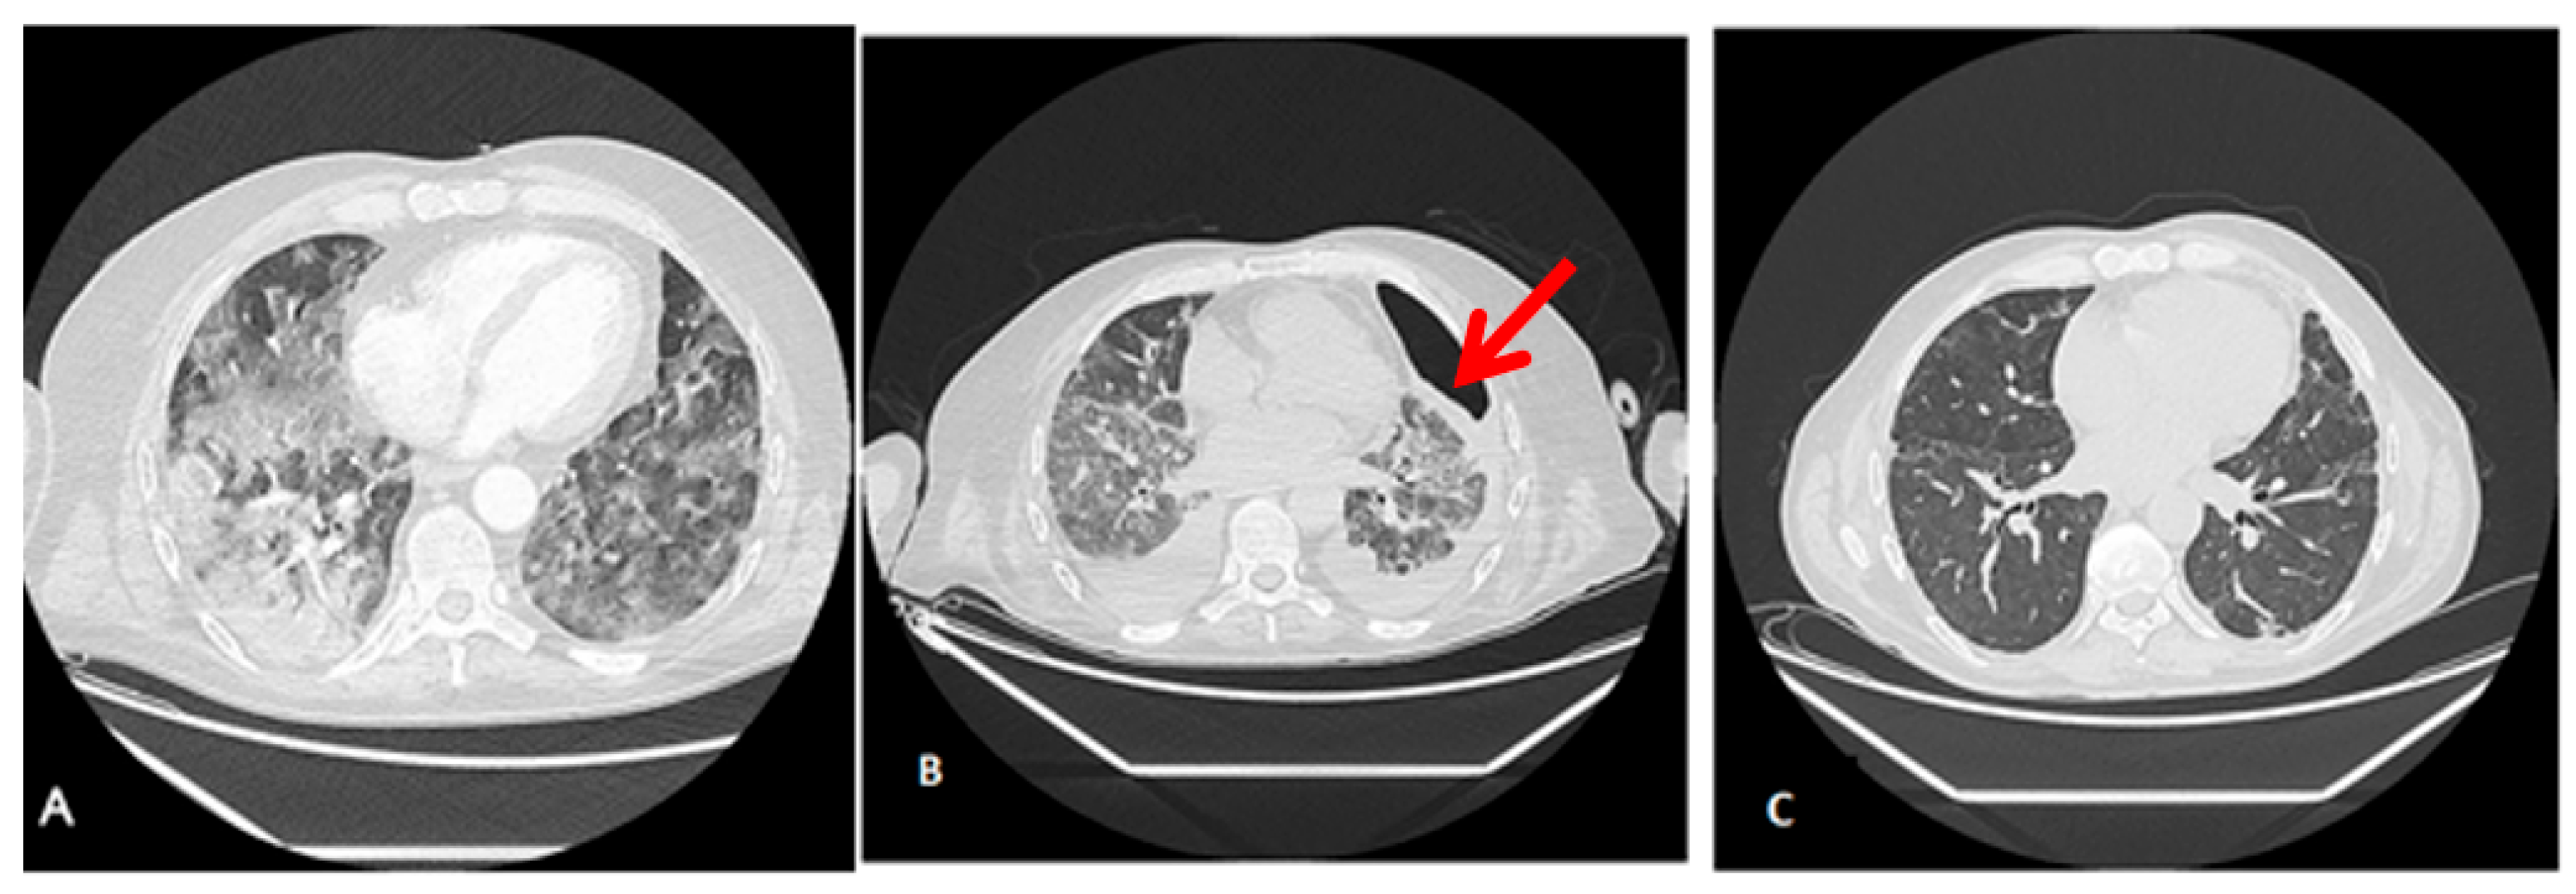

3.3. Radiological Findings